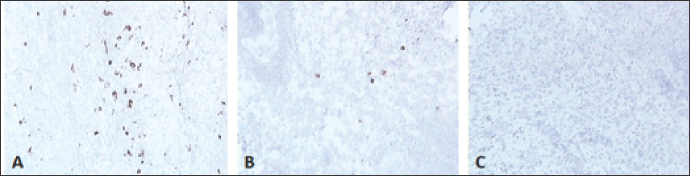

Fig. 6. Skin sections of birds stained with the monoclonal antibody AV296 days post inoculation with (A) PBSa, (B) PHA, and (C) FP9. Positive staining for CD4+ cells appeared brown (100x magnification).

CD4+ T cells

Skin sections were stained with the monoclonal antibody AV29, which recognizes CD4+ T cells (Davison, IAH) (Fig. 6). Numbers of CD4+ cells increased slightly from 2 dpv compared to birds inoculated with PBSa and PHA. CD4+ T cells gradually increased to reach a peak at 6 dpv at the site of vaccination in the skin, followed by a gradual decrease from 8 dpv onwards (Fig. 7).

CD8+ T cells

Skin sections were stained with the monoclonal antibody AV14, which recognizes CD8+ T cells (Tregaskes et al., 1995) (Fig. 8). CD8+ cells increased rapidly and sharply starting from 4 dpv, and reached a peak at 6 dpv at the site of vaccination in the skin, and then dropped rapidly from 8 dpv onwards (Fig. 9).